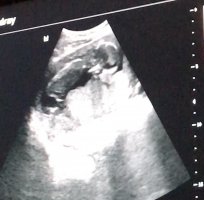

Ben yabancı sitelerden bu konuda yardım istedim hemşireyim bu arada bebeğin elini nub diye değerlendirdiler ben açıkçası işaretlediğim yerin nub oldugunu düşünüyorum siz de bi bakarmısınız

Merhaba, yüklemiş olduğunuz resim ışıktan çok fazla zarar görürmüş açıkçası nub çıkıntısı anlaşılmıyor bu nedenle bebeğinizin cinsiyeti hakkında net olarak tahminde bulunamıyoruz.